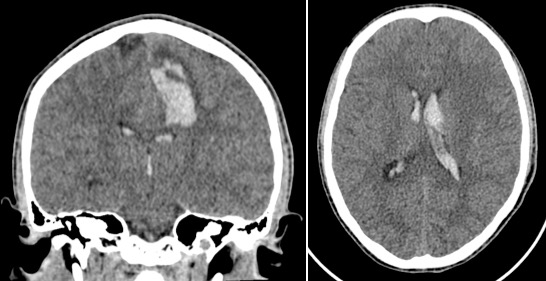

certains MAV, comme celle présentée ci-contre, ne peuvent pas être traitées sans infliger des séquelles majeures et doivent être respectées. on doit donc se contenter d’un traitement symptomatique.